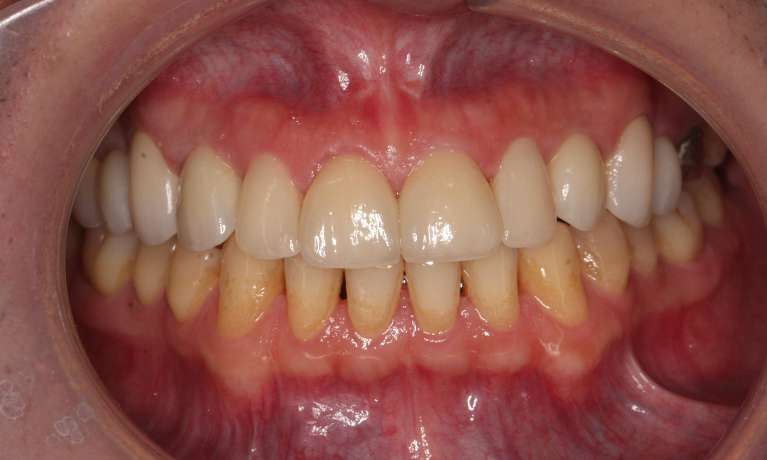

This adult patient had heavily restored discolored and defective upper front teeth. Their upper front four teeth were rejuvenated with new crowns to give the finished smile.